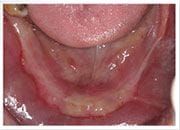

植牙過程

治療前

植入植體